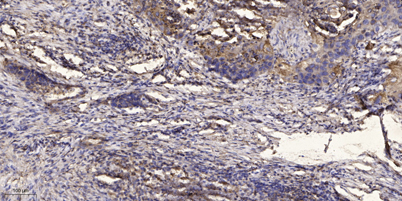

Applications IHC

Recomended Dilution IHC-p 1:50-300